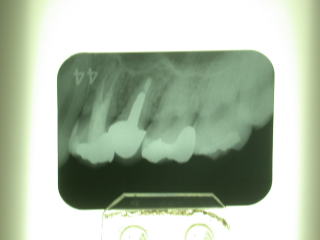

通法とおりレントゲン写真を撮影し、歯根の状態を確認します。このような場合反対側も同様な場合も多いと思われますが、右側は特に異常は認められませんでした。